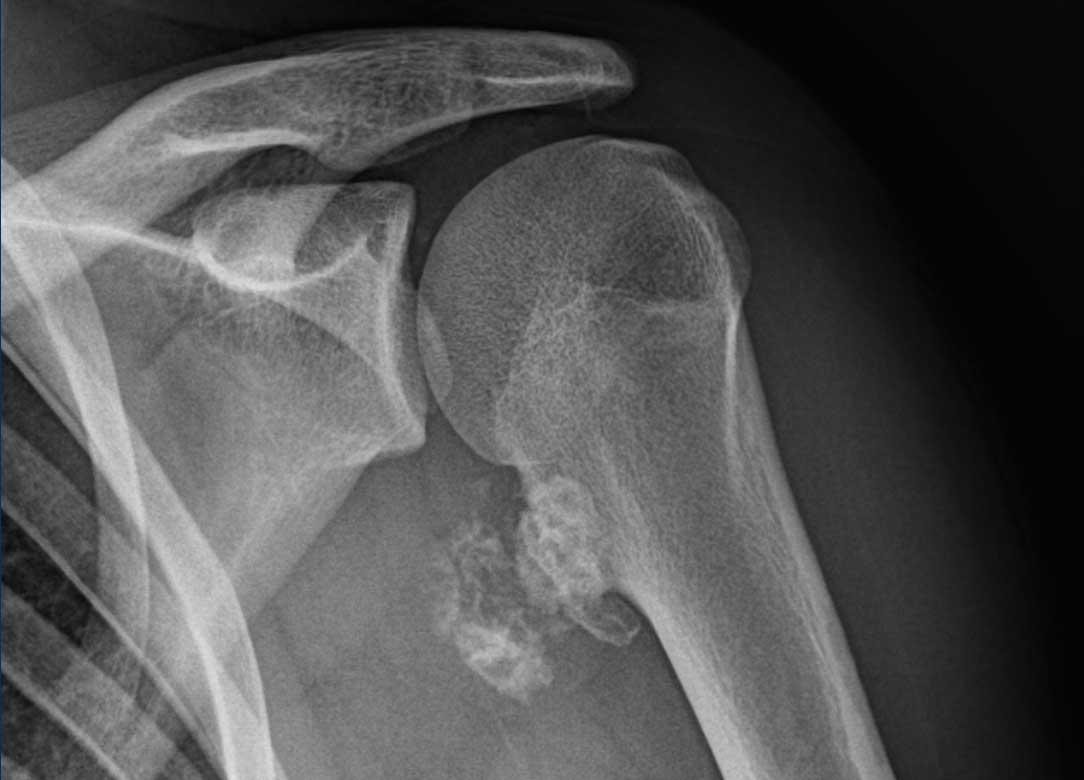

Hình ảnh X-quang này của bệnh nhân 17 tuổi

có biểu hiện đau vai trong 2

tháng.

Hình ảnh

Có một tổn thương có cuống xuất phát từ hành xương đầu trên xương cánh tay.

Cuống xương cho thấy sự liên tục của tủy xương và một mũ sụn bên trên chứa các vôi hóa dạng sụn.

Những đặc điểm này điển hình cho u xương sụn (osteochondroma).

Trên phim X-quang, phần sụn mũ đã vôi hóa và do đó có thể nhìn thấy được khá lớn, đó là lý do tại sao MRI được thực hiện để đo chính xác độ dày của mũ sụn.

Continue with the MR-images…

Độ dày của mũ sụn được đo vuông góc với vỏ xương trên chuỗi xung T2.

Hình ảnh T2W trục ngang có kỹ thuật ức chế mỡ cho thấy u xương sụn ở mặt sau đầu trên xương cánh tay trái với độ dày mũ sụn 22 mm.

Trong các tổn thương

có mũ sụn > 2 cm, phẫu thuật cắt bỏ được thực hiện để loại trừ

u sụn ác tính.

Khối u đã được cắt bỏ và

kết quả giải phẫu bệnh phù hợp với u vỏ thượng thận ngoại vi.